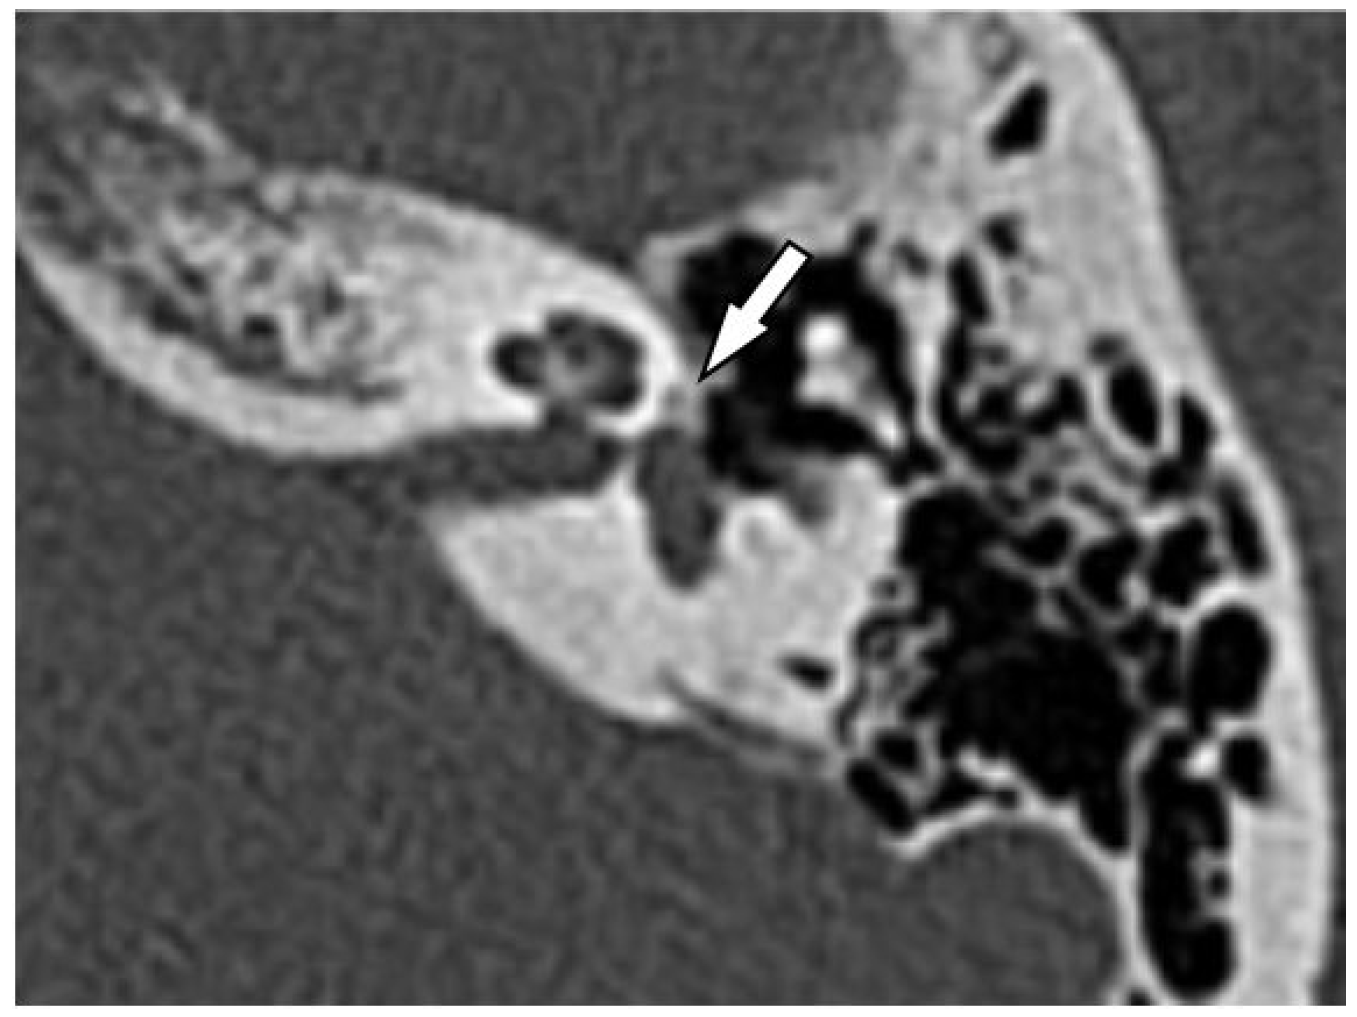

Axial CT image at the level of the stapes footplate / oval window Stapes Bone Radiology Stapes was studied in the stapes axial plane obtained after a triple orientation. It features a link transmitting vibrations from the aerial environment of the middle ear to. Twenty seven patients underwent ossicular reconstruction. The stapes is a bone in the middle ear that plays a crucial role in hearing. The base of the stapes rocks in and out against. Stapes Bone Radiology.

Case 226 Oval Window Atresia Radiology Stapes Bone Radiology The anatomy of the temporal bone is complex, and postoperative imaging evaluation of this bone can be challenging. The stapes is the smallest bone of the human body. It features a link transmitting vibrations from the aerial environment of the middle ear to. Progressive conductive hearing loss is the major clinical symptom of otosclerosis, which causes stapediovestibular ankylosis (fig. The. Stapes Bone Radiology.